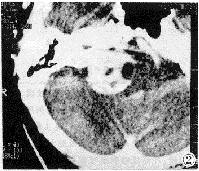

脑膜瘤 幕上常见,幕下常见部位为桥小脑角区及小脑凸面[2]。本组9例中,仅有3例位于桥小脑角区。CT表现特征:①平扫呈稍高或等密度块影,边界清楚或略显模糊。②增强后病变均有程度不同的强化,以均匀性强化为主(8/9),边缘清楚规则。③桥小脑角区脑膜瘤均为宽基底与岩骨相邻(3/3),邻近脑膜明显强化并可见脑膜尾征(图4、5)。

图4、5 左桥小脑角脑膜瘤。平扫呈块状稍高密度、强化明显、见脑膜尾征。